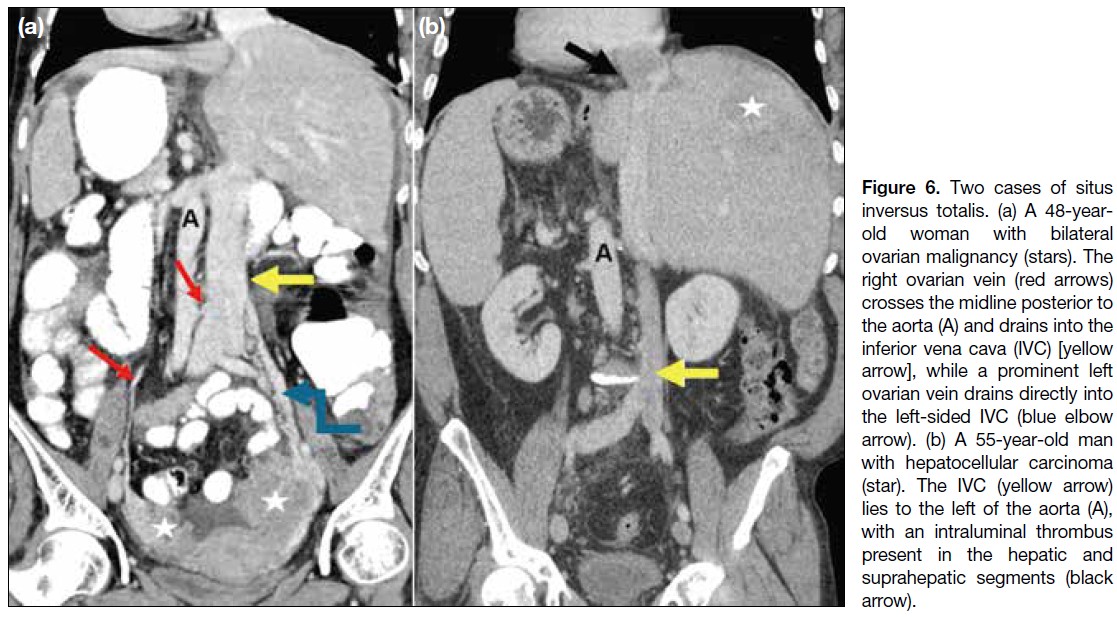

Figure 6. Two cases of situs

inversus totalis. (a) A 48-year-old

woman with bilateral

ovarian malignancy (stars). The

right ovarian vein (red arrows)

crosses the midline posterior to

the aorta (A) and drains into the

inferior vena cava (IVC) [yellow

arrow], while a prominent left

ovarian vein drains directly into

the left-sided IVC (blue elbow

arrow). (b) A 55-year-old man

with hepatocellular carcinoma

(star). The IVC (yellow arrow)

lies to the left of the aorta (A),

with an intraluminal thrombus

present in the hepatic and

suprahepatic segments (black arrow).